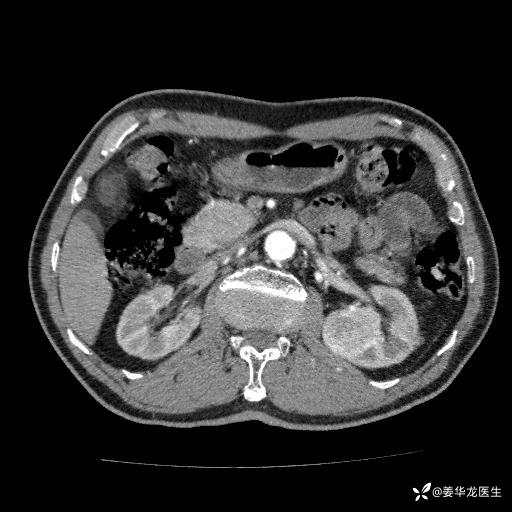

左肾中心型肾门部肿瘤39mm×34mm×36mm,右肾GFR25ml/min,部分切还是全切?

患者75岁老年男性,体重50kg,无高血压、肾病、糖尿病等基础病,检查发现左肾中心型肾门部肿瘤,右肾GFR只有25ml,无肉眼血尿,无镜下血尿。入院验血常规检查均正常,包括肾功能,肌酐102.7umol/L.

二、左肾肿瘤与左肾集合系、左肾动静脉关系密切,左肾部分切除术可行吗?成功率有多大?成功部分切后,肾功能还有多少?